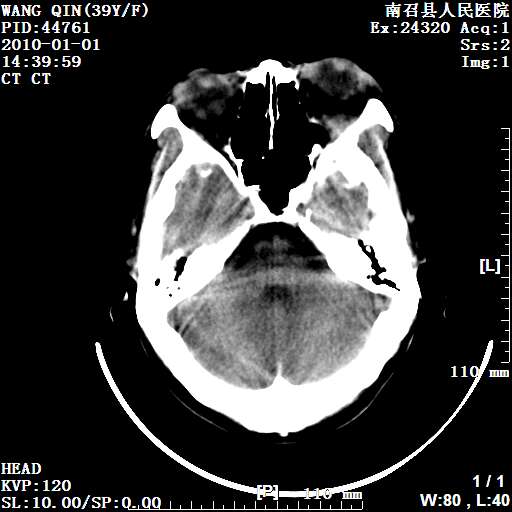

以下是引用随光逐影在2010-1-22 9:03:00的发言:[br]考虑左侧中颅窝(蝶骨翼区)脑膜瘤侵犯蝶骨翼并突入左侧眼眶。

以下是引用水过无痕在2010-1-22 14:55:00的发言:[br]一、定位:颅外占位;二、定性:恶性可能性大;三、组织来源:来源于左侧眼外直肌或其他部位;考虑为:横纹肌肉瘤>转移瘤>脑膜瘤.